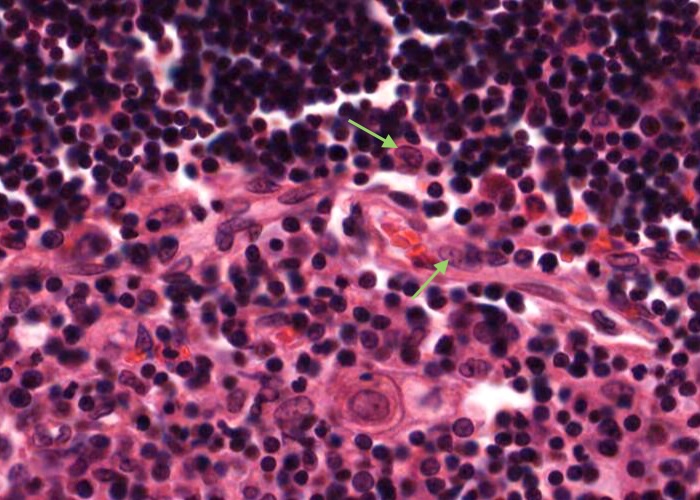

A type III epithelioreticular cell can be seen at the boundary of the cortex and the medulla. They are similar to type 1 cells in functioning as a barrier that isolates developing T- cells between the cortex and medulla.

A type IV epithelioreticular cell can be seen at the boundary of the cortex and the medulla close to the locatioons of the type III epithelioreticular cell. Together these cells interconnect and function as a barrier that isolates developing T- cells between the cortex and medulla